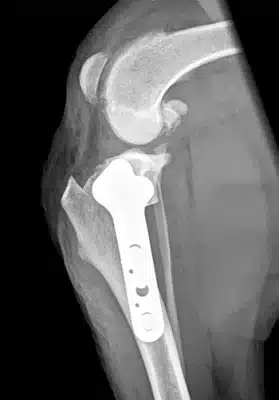

Tibial Plateau Levelling Osteotomy

The most effective surgery for pets suffering with cruciate disease.

xray image

Cruciate disease is the most commonly treated orthopaedic condition in dogs. The term is used to describe lameness attributable to partial or complete rupture of the cranial cruciate ligament with resultant instability of the stifle (knee joint) and development of osteoarthritis.

Eastcott Veterinary Referrals offers TPLO surgery which is the current Gold Standard treatment available.